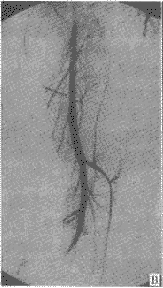

中国临床解剖学杂志000350 患者男,35岁。因左小腿被石块砸伤2 h于1998年12月5日入院。查体:左小腿中下1/3处不规则裂口,畸形,异常活动,有碎骨块外露,足远端血运良好。X线检查示左胫腓骨粉碎骨折。诊断:左胫腓骨开放粉碎骨折。急诊清创外固定支架固定。术后左小腿中下1/3处胫前皮肤坏死,约8 cm×10 cm,行右侧胫后动脉为蒂的小腿内侧皮瓣游离移植修复。术前检查右足背及胫后动脉搏动良好,做交通试验示足背及胫后动脉通畅。术中见右胫后动脉于小腿下1/3处与胫神经分离并走向前外侧,到小腿骨间膜处再折回内踝后与胫神经一同进入踝管。将皮瓣游离,于皮瓣近端(相当于小腿中上1/3交界处)阻断胫后动脉,发现足背及胫后动脉搏动消失,足血运消失。考虑胫前动脉有变异,改取右股前外侧皮瓣修复。后经DSA动脉造影检查示右胫前动脉缺如,动脉仅延续为胫后动脉,胫后动脉在腓骨小头下平面分出腓动脉(附图A、B);胫后动脉在小腿中下1/3处走向前外侧呈倒“Y”形分为2支,一支较细向前延续为足背动脉,另一支较粗走向内后,在足底分为内外侧2个终支(附图C、D)。

附图 胫后动脉与足背动脉发自腘动脉